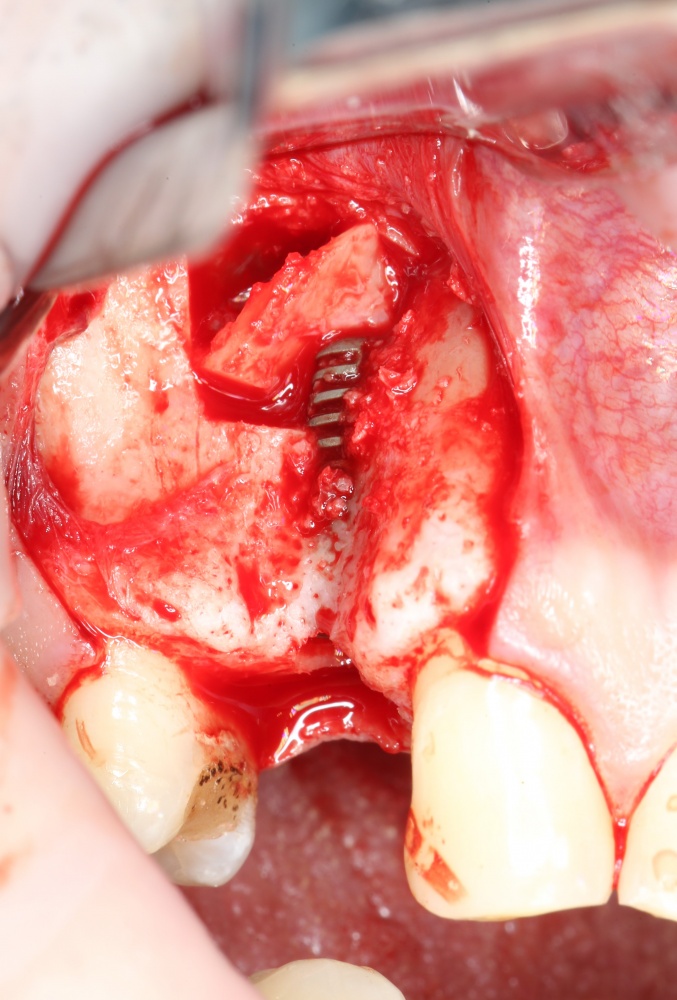

Нюансы начинаются с обработки принимающего ложа. Да-да, уважаемые друзья, одна из причин некроза блоков, их чрезмерной атрофии и прочих проблем — в отсутствии обработки принимающего ложа. Некоторые делают дырки, но правильнее и эффективнее поступить так:

то есть, просто снять слой кортикальной пластинки с участка, к которому будет фиксироваться костный блок. Почему? Читайте здесь>>.

Вторая особенность — мы не адаптируем и не обрабатываем костный блок invitro, а фиксируем его так, как есть:

после чего обрабатываем — доводим до окончательной формы альвеолярного гребня:

Далее, можем приступить к установке имплантатов. Разумеется. по хирургическому шаблону:

Последняя картинка даёт представление о том, какой объем костной ткани мы «нарастили».